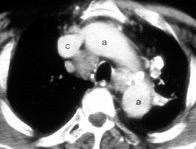

C